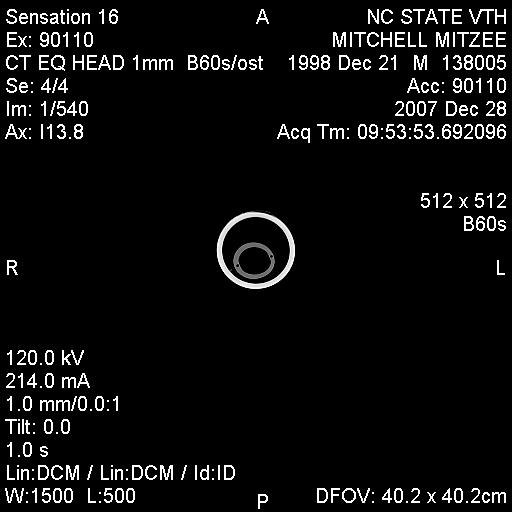

Posted on Sunday, Jun 24, 2007 - 3:39 pm: Greetings Everyone,I have finally received some of Mitzee's xrays, though it appears that I'm missing several... hmmm... Anyway, I thought I would give everyone an update. After two weeks of inpatient care (IV antibiotics, anti-inflamatory agents, a few different wound site I&Ds, several xrays and another fistulogram, etc...), she was discharged on 6/7/7. The final fistulogram showed NO evidence that the draining sinus tract communicated with the adjacent tooth root (4th premolar), but, rather, seemed to travel to the empty alveolar socket of her previous surgical site (the removed 3rd premolar). I had decided I did not want to attempt to manage her on my own, so I arranged to board her and Rorie at a facility owned by an equine vet, kind of like a lay up hospital situation... She's been getting daily assessment and care of her wound, the barn has a great fly control system and, so far, she usually goes out at night and stays in during the hot day. Plus, when she and Rorie are out, they're with other mare/foal pairs and that's a nice bonus for Rorie. Mitzee's eating well, her weight is good, and her activity is normal. And, though tissue healing is occurring, significant swelling of her left submandibular area persists and there are two remaining tracts that drain purulent material, though it is less than previously observed. I have decided to see how things go for awhile and "embrace" this conservative approach... clearly, the surgeon was not interested in pursuing more surgery at the time of her discharge, though when I corresponded with him recently (and showed the same pictures I am posting below) he suggested we get a CT scan. Of course, a CT scan appears to require general anesthesia and I would have to take her to a larger referral, probably academic, center. Based on where I am in VA, the closest facilities are NC State in Raleigh, NC, Marion duPont Scott in Leesburg, VA, or VA Tech in Blacksburg, VA... I do still worry that there's something "left behind" in the wound, perhaps a necrotic bone fragment???, that is continuing to feed this low level infection... At this point in time, she is almost 6 weeks postop from her initial surgery to remove premolar #3... Rorie was 8 weeks old last Tuesday... What does everyone think???? Thanks! Martha

Posted on Sunday, Jun 24, 2007 - 7:09 pm: I presume the folks who look at the original and complete set of radiographs, see no dead bone? Martha, considering everything, the swelling itself is not a bad sign and may take time to resolve. The radiograph is difficult to evaluate as it seems to lack much detail, possibly a problem with the generalized swelling. The parts we can make out look ok. Most important their is still purulent drainage, indicating the bodies attempt to rid itself of infection and/or necrotic material. As long as it is improving the conservative approach may work.DrO |

Posted on Sunday, Jun 24, 2007 - 8:57 pm: Thanks Dr. O and Everyone,Sorry, I know the film is somewhat poor... the surgeon's office girl sent me several films via an email attachment, so I wonder if when I downloaded them and reduced their sizes maybe I lost some resolution??? Hopefully, I will get a CD of all these films and can post better copies for your review... The surgeon reviewed all the films with me on the day of Mitzee's discharge and he felt pretty comfortable with everything being O.K. at that time, but, recently, when he saw the pictures I posted above, he suggested we get a CT scan... Dr. O, what's your take on that???... and, BTW, since you're in NC have you had "experiences" with NC State's vet school??? They're only down I-95/I-85 about 120 miles or so from Richmond and it would be a manageable trip to make, if needed... Regarding the issue I raised previously about hyperbaric oxygen therapy, I did talk to UT Knoxville and found out that their old chamber (a portable one) is not operational now in order to be replaced with an upgraded chamber (one that is permanently in place), hopefully sometime by the end of July... So, if there's ongoing evidence of infection, I still want to keep HBOT in mind... Thanks! Martha |

Posted on Monday, Jun 25, 2007 - 1:39 am: The picture quality IS poor, but it almost looks like there is some healing going on. |

Posted on Thursday, Dec 27, 2007 - 10:48 pm: Hey HA friends,Just wanted to say that Mitzee and I have arrived in the Tarheel state tonight! In a nutshell, for the past several months, Mitzee has continued to have intermittent serosanguinous vs. scant purulent drainage from her submandibular area and a significant ?fibrosed deformity of her jaw, though really no other indications of clinical problems... she's chewing well, weight is good, afebrile, etc... Sometime back in the summer, our equine surgeon had suggested that we undergo a CT scan (you guys may remember that even though Mitzee had significant purulence and edema following her initial surgery in May, the surgeon was very reluctant to "re-explore" the area due to the difficulty of that first surgery and the lack of evidence from her contrast fistulograms that the adjacent tooth root was involved in any infection)... So, though I had hoped to have her undergo this in the summer, NC State's Vet School was awaiting a "functional" table to use for equines in the scanner; and, though I was considering going to VA Tech instead, I had that little foot fracture in July which pretty much impaired my equine activities for several months. Given that she looked so good clinically, I decided to wait for NC State's table to be operational, but also given the continued appearance of the submandibular drainage, I still wanted to rule out any retained ?necrotic bone fragment or area of osteomyelitis in her mandible. So, tomorrow is the big day for the CT scan. The CT scan findings will direct any subsequent care, more surgery vs. medical therapy vs. nothing needed... I hope to get the CT films and post those sometime this weekend... wish us luck! Martha P.S. And, BTW, the other really wonderful thing is that I weaned baby Rory about a month ago (I changed the spelling of his name when I submitted his registration papers)... and in doing so, I moved Mitzee to another facility; well, I've spent alot of time with her over the past month and we have actually started to bond; she clearly has begun to trust humans and, in particular, me! Just the fact that I can groom her completely, touch every area of her face/head, even the submandibular area without too much protest, pick up her hooves (briefly) is all really wonderful! The new barn where I'm boarding her is a very busy hunter/jumper/eventing barn that gives a huge number of lessons, primarily to kids; Mitzee has really gotten desensitized to all the chaos that goes on and all the little girls at the barn just love her (she is the only Appaloosa there and her "rescue" history has made her interesting to everyone there)... I have really begun to marvel at the smarts this mare has and how willing she is to tolerate many different situations; I really believe that she will be under saddle in the next several months and that she will make a wonderful and safe mount! |

Posted on Saturday, Dec 29, 2007 - 9:43 am: Thanks for the update Martha and am surprised to hear you are having problems. The lack of problems on the last radiograph suggest this should have healed in most cases. There are two explanations:1) a foreign body, possibly a dead piece of bone 2) a resistant infection either bacterial or fungal Hopefully the CT scan will help better define the problem so it can be fixed but surgery with thorough debridement and good microbial work up are likely to be required whatever they find. Keep us appraised Martha. DrO |

Posted on Saturday, Dec 29, 2007 - 8:14 pm: Well, thanks for everyone's comments!Here's the scoop... the CT clearly showed infectious "involvement" of the adjacent tooth (left lower 4th premolar), though fortunately, the root and the pulp appeared to still be healthy; also, an area of the mandible inferior to the previously removed tooth (left lower 3rd premolar) had a "sequestrum", sort of under the now empty alveolar socket, which is well healed. So, immediately following the CT, after the surgeon reviewed it with the radiologist, Mitzee got moved to the OR (still under general anesthesia) and debridement of the affected areas began. Once the surgeon performed an oral exam, he was also able to demonstrate an orocutaneous fistula, corresponding to the exact area on her lateral jaw where she has had continued intermittent drainage for the past several months. The surgery and anesthesia were uneventful and she looked great when I left her last night (I'm on call today at work)... I will probably be able to pick her up as early as tomorrow, but that will depend on how much sleep I get tonight. Hopefully, I will be able to post some pictures of her xrays and CT scan for everyone to see... NC State has this great program, called Amicus, that "converts" the two dimensional information from the CT scan into three dimensional, COLOR, pictures and WOW, what information they reveal... just remarkable (I doubt I will be able to post any of those pictures due to the licensing issues with the software company)... Also, the veterinarians and staff of NC State have been AWESOME... I'll try to post pictures tomorrow... Martha |

Posted on Tuesday, Jan 1, 2008 - 11:08 pm: Hey Everyone,Sorry for the delay in posting the images... Mitzee was discharged on Sunday (POD 2) and I DrOve down to NC, picked her up, and travelled back to VA in the worst pouring down rain (not complaining, we still do have DrOught conditions a bit...) Anyway, I was on call the next day (New Years eve) and had a killer night, so I am still kinda brain dead today... I've managed to crash my laptop several times with the disc I was given at NC State... just wondering if it has anything to do with my new laptop OS, Vista, but now, finally, I've managed to load some of the study pictures onto my old laptop (hopefully the keyboard won't quit like it did this summer). The plain xray is not great... possibly me altering it in the download process??? Anyway, it is a lateral so you see both sides of the jaw and you have to focus on the near structures (the left side), not the far ones (the right side); basically, it shows distortion of the the left lower premolar #2, which has occurred following removal of #3 last May, and compensatory changes in the left upper arcade (see the big ramp/points above). The few CT views I've uploaded show extensive bony proliferation and periosteal reaction of the left hemimandible, an absent left lower 3rd premolar tooth, as well as some radioopaque densities below this area, presumed to be ?tooth fragments or cement debris following the previous surgery; there is one particular linear density located in the center of this area that was felt to represent a possible "sequestrum" and was removed... also, you can see a radiolucent tract that exits the lower portion of the left hemimandible below the empty alveolar area of the absent 3rd premolar. A lytic lesion is seen associated with the lateral aspect of left lower 4th premolar near the gingival margin and another draining tract travels between this front/rostral portion of the left lower 4th premolar tooth and the lateral aspect of the mandible; my discharge papers state that the CT findings "are consistent with peridontal abscessation and a draining tract", however the surgeon believes the root and pulp of the left lower 4th premolar tooth are still healthy, so we may have a ?50/50 chance of saving that tooth. I have also attached a few other pictures of Mitzee undergoing her CT scan under general anesthesia, her recovery from GA, and a view of the her face following the surgery where the diseased areas were debrided. Her discharge papers note the final diagnosis as "chronic osteomyelitis of the left mandible and peridontal disease adjacent to left mandibular premolar tooth #4". I'll keep everyone posted on her recovery. Thanks!!! Martha

Posted on Monday, Jan 7, 2008 - 4:56 pm: O.K., I am going to try and load the CT images again... please refer to my descriptions of them above. Also, the surgeon from NC State called me today and reported the results of the cultures taken during surgery; Mitzee has grown two types of anaerobic, gram negative rod bacteria, a Prevotella "species" and Fusobacterium nucleatum. He said that he had not had a Prevotella isolated from equines in the past, but that the Fusobacterium is a common oral bacteria in a number of species.... Now, the plan had been for Mitzee to receive two weeks of postop antibiotics, trimethoprim/sulfamethoxazole (Bactrim DS) and when I brought her home on POD#2, I was able to give her the PM dose by syringing paste directly into her mouth (she did protest a little); for the next 24 hours, I was on call and during my absence the barn staff failed miserably in getting any drug into her! I certainly didn't want any of the barn staff to sustain injuries, nor did I want Mitzee to be hurt (apparently, she got into her rearing mode...), so I spoke with the surgeon then and he said I could forego her oral antibiotics (afterall, the surgical debridement was the "definitive" therapy!). Today, he mentioned that metronidazole (Flagyl) was the typical antibiotic for anaerobes, but that horses tolerate it even less than the Bactrim she had been on... so, since he felt good about the debridement, we are not treating her with antibiotics. The plan is to (as long as she looks good "clinically") take her back to Raleigh in about 4 weeks so he can examine her oropharynx and HOPEFULLY see that her orocutaneous fistula is HEALED and that the left lower premolar #4 is still O.K.!!! I'll keep everyone posted!Martha P.S. Keep in mind, when looking at the scans below, you are looking at a "cross-section" or axial image of the head, UPSIDE down... remember that she was laying on her backside to undergo the scan... also, the right side of the image is Mitzee's left side... notice the dramatic difference between the two sides, i.e., each hemimandible...

| Moderator: DrO |

Posted on Tuesday, Jan 8, 2008 - 8:07 am: They really caught the fistula and infected mandible well. Good luck with the surgery outcome Martha.DrO |